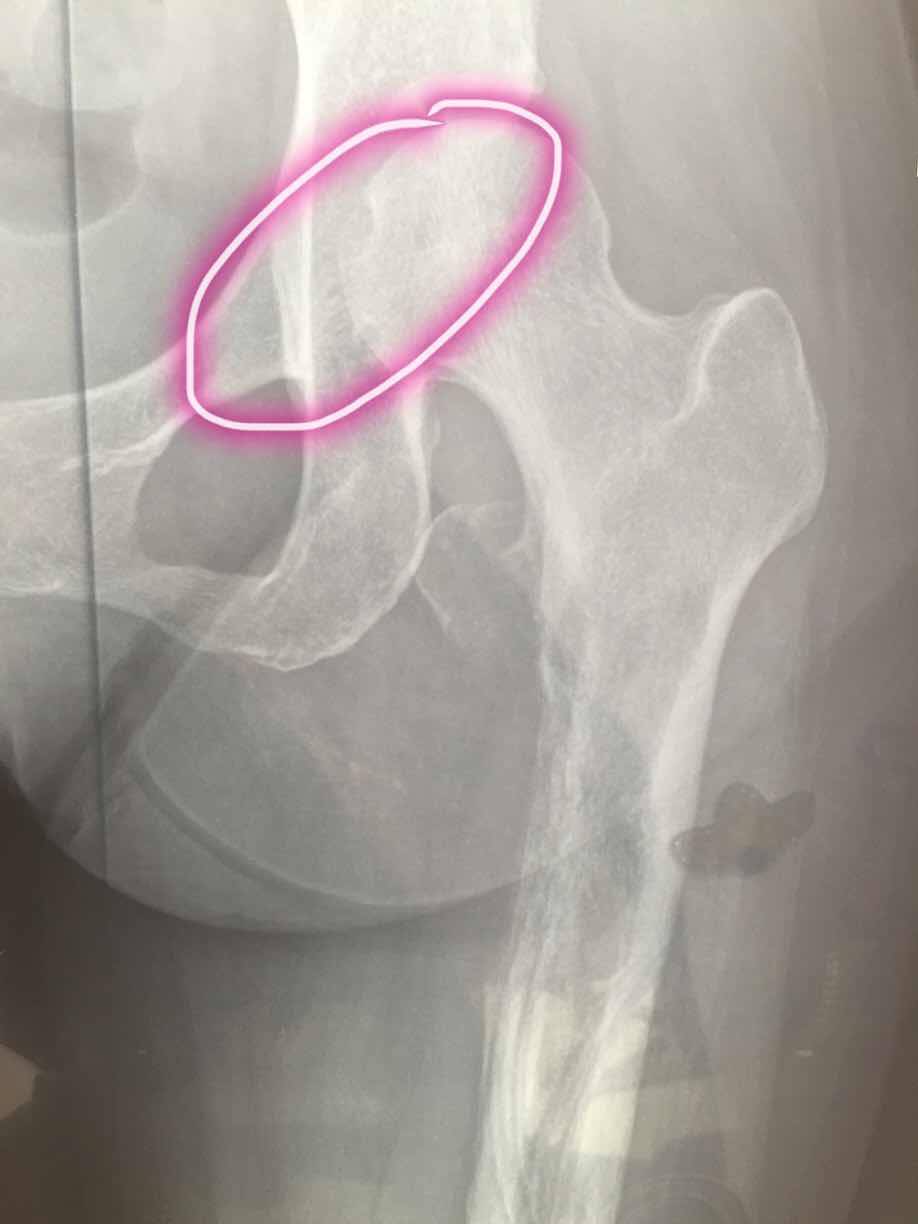

妈妈肺腺癌晚期骨转严重大腿根骨裂求大家帮忙

妈妈年前左大腿总疼,去医院检查说是腰间盘突出,在家卧床躺了3个月,前两个月还好,后一个月疼痛难忍。再去检查才发现是肺癌转移,然后主要转移到腿部比较严重,大腿根在不知情的情况下还掰了一下,造成了骨裂。去医院检查,骨科医院说是腿能做手术,但是还是建议先控制肿瘤,去了肿瘤医院,肿瘤医院说是腿没办法治疗了,因为妈妈大腿掰了一下已经目前卧床影响行走了,1月4号确诊,半月后开始打了骨转针,和吃了靶向药易瑞沙,我家是19突变,在这之前腿疼痛难忍,吃了易瑞沙就不疼了,但是还是由于大腿根骨裂影响行走,目前妈妈食欲还不错,睡眠也还好,就是躺着总说很累,求大家帮帮我,有懂ct这方面的也可以帮我看看,妈妈的腿能不能自愈,毕竟没有骨折。钙片骨转针一直在吃。求求大家帮帮忙。